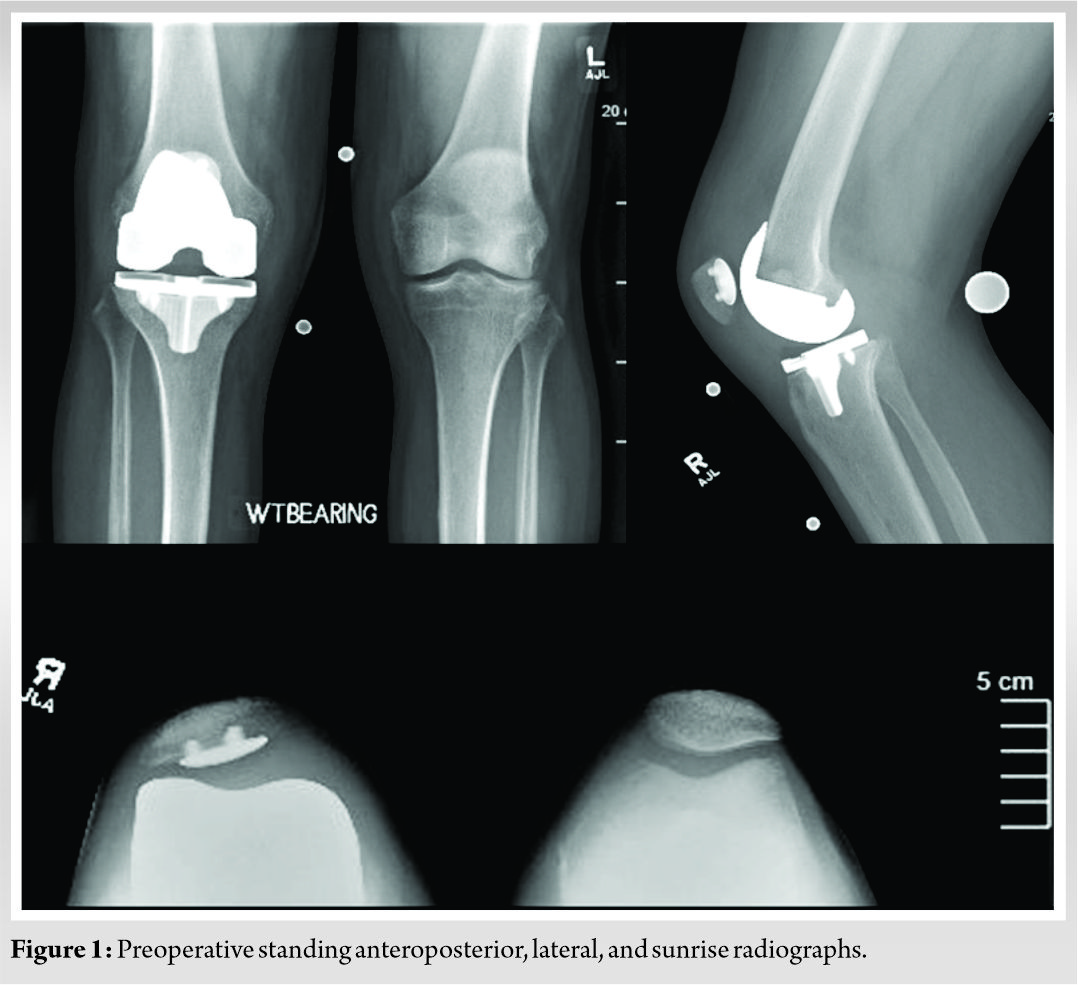

This is a case of a 68-year-old male who presented to our institution for evaluation of the right TKA. He underwent his index TKA in December 2018 at an outside institution. He did not have any significant medical history. He had a good recovery after surgery, but 6 months postoperatively he developed discomfort in the right knee. He presented to our office approximately 2 years after his index procedure for evaluation of his right knee after failing conservative management (Fig. 1). He subsequently underwent testing to rule out component loosening and infection. His clinical examination as well as a bone scan suggested loosening of the tibial component. His laboratory workup including erythrocyte sedimentation rate, C-reactive protein, white blood cell, and joint aspiration was negative for prosthetic joint infection. After a lengthy discussion regarding the risks and benefits of the procedure, he elected to proceed with right rTKA with Mako robotic assistance. A Stryker Triathlon revision knee system was planned to be used for this case.